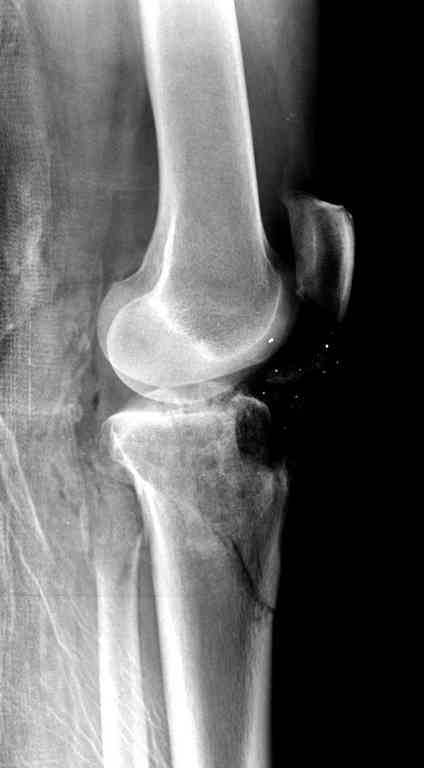

Пожалуйста, снимки.

На вашем снимке из-за ротации трудно угадать положение пластины, и желательно сделать снимок с захватом верхнего участка бедра.

Одинокий кортикальный шуруп не удержит тибиальный бугор, сустав тибиал плато оставлен без репозиции и фиксации.

План с протезированием чересчур агрессивный, больная слишком молодая. В данный момент для удержания конструкции необходимо установить наружный фиксатор между бедром и голенью. Обработку продолжать с применением антибиотиков и вакуумирования.